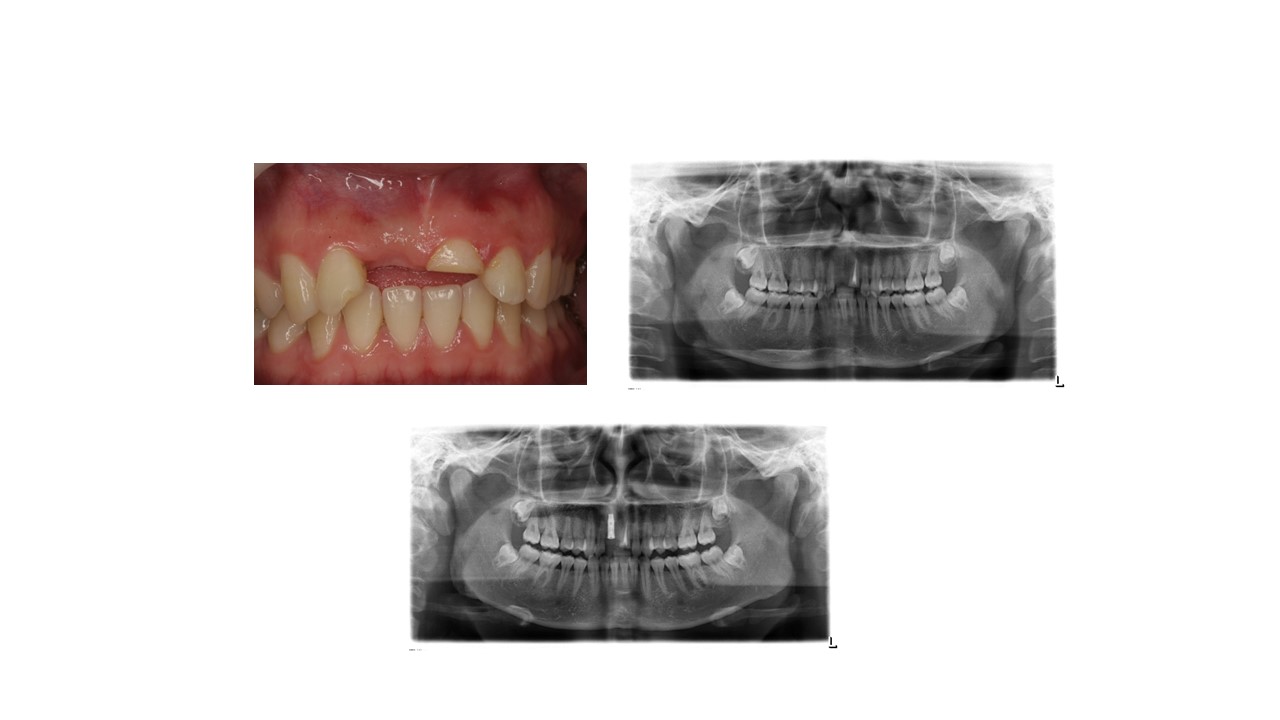

种植科普

智齿是否都需要拔出